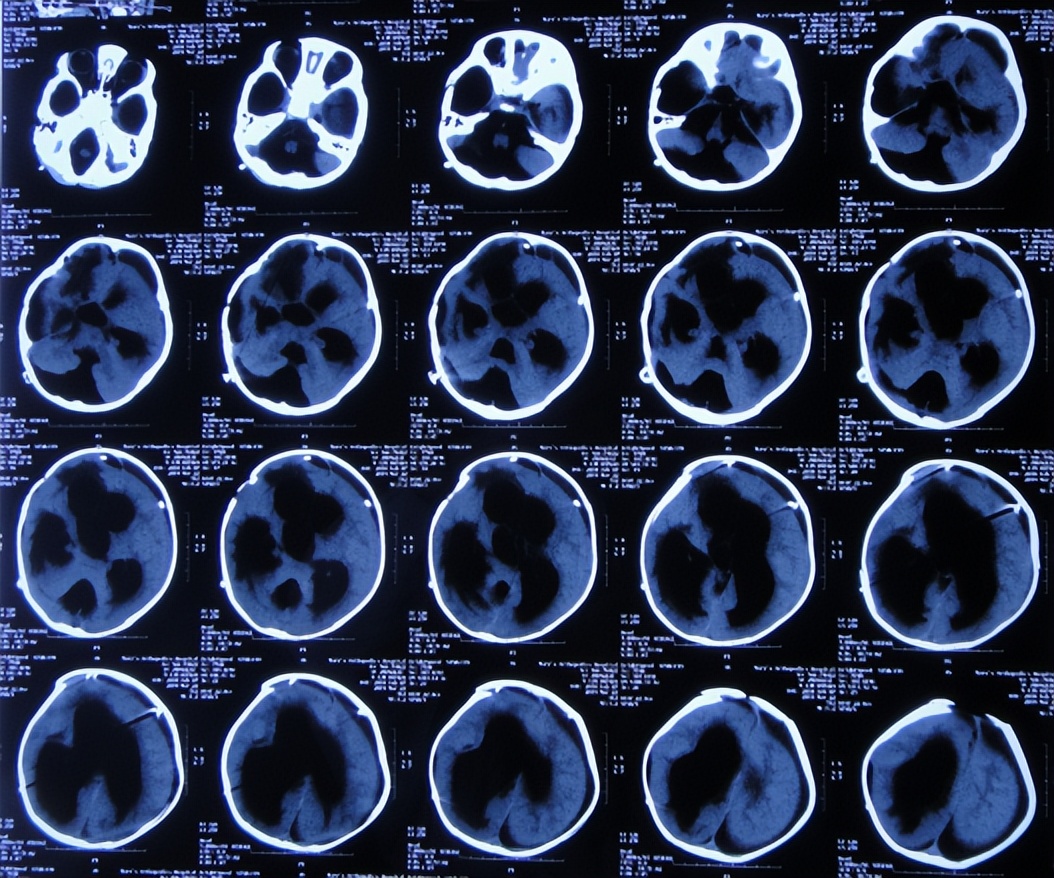

患儿2018年2月份,早产1月,剖宫产出生,出生后未见异常;患儿3个月大起,家属发现患儿头围较同龄幼儿大点,未给予重视;直到7个月大时,因发育迟缓自己不能坐,且头围进行性增大,于2018年9月11日,至当地第1家医院陕西省西康市白河县某医院,检查头颅CT发现双颞叶蛛网膜囊肿、脑积水( 图-1 )。

图-1: 2018年9月11日头颅CT